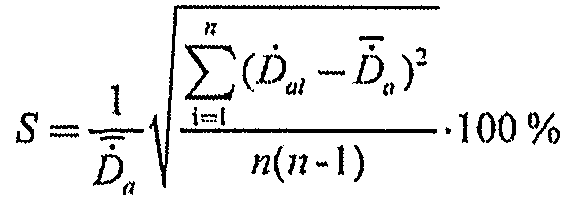

6.2. Среднее квадратическое отклонение среднего арифметического (далее - СКО среднего) результата измерений, S, %, для дозиметров, измеряющих МПД и МАД, рассчитывают по формулам (5, 6):

(5)

(6)

Для дозиметров, индицирующих коэффициент вариации и(или) статистическую погрешность результата измерений, можно считать, что СКО среднего равно коэффициенту вариации и(или) статистической погрешности.

6.3. Стандартную неопределенность, обусловленную источниками, имеющими случайный характер, %, принимают равной среднему квадратическому отклонению S, %, рассчитанному по формулам (5) или (6):